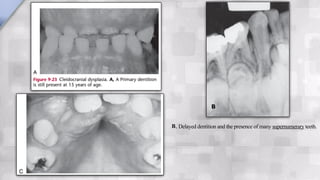

The development of the dentition is delayed. Complete primary dentition at 15 years of age resulting

One of the important distinguishing characteristics is the presence of supernumerary teeth.

B, Delayed dentition and the presence of many supernumerary teeth.

A rare congenitalsyndrome that has dental significance. Transmission of the condition is by either parent to a child. CCD can also occur sporadically with no apparent hereditary influence. The diagnosis is based on the finding of an absence of clavicles. The development of the dentition is delayed. Complete primary dentition at 15 years of age resulting from delayed resorption of the deciduous teeth and delayed eruption of the permanent teeth is not uncommon. One of the important distinguishing characteristics is the presence of supernumerary teeth.  CLEIDOCRANIAL DYSPLASIA

B, Delayed dentitionand the presence of many supernumerary teeth. B